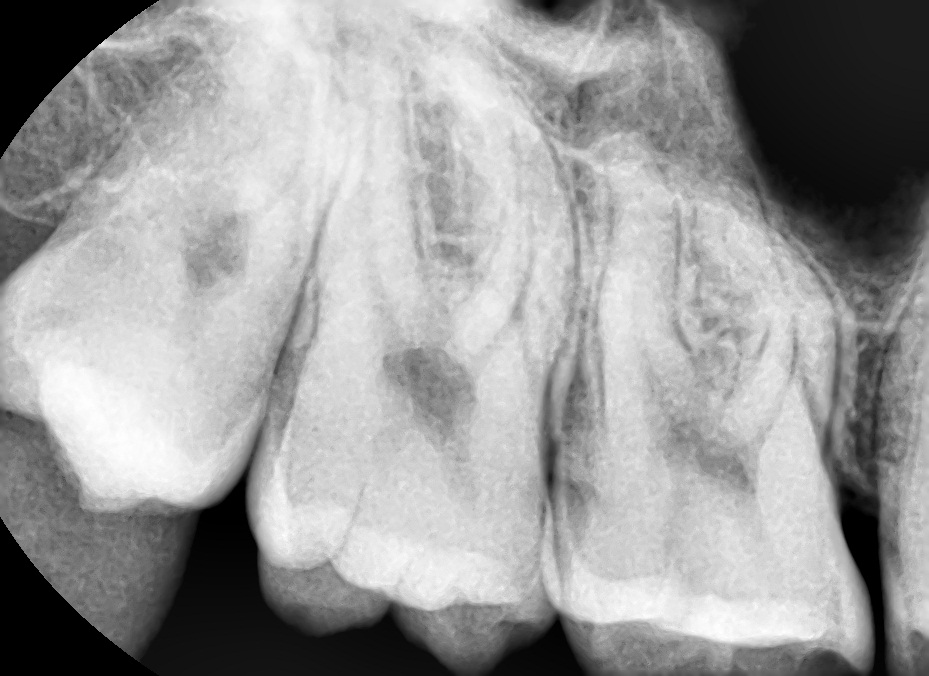

3주만에 충치가 상아질을 뚫을수있나요?

3년간 양치안했더니 법랑질에 국한된 충치가생긴 어리석은 청년입니다. 요즘도게을러서 사진속 치아상태에서 3일에 한번주기로 꼼꼼하게 양치와 치실질을 진행했었는데 3주정도 되었습니다. 3일에 한번씩 꼼꼼하게한정도로는 3주동안 충치가 더 번졌을 가능성이 높나요?

• 1번 째 사진

교합면(씹는면) 충치는 그렇게 빨리 진행되지는 않습니다. 인접면 충치의 경우 법랑질 부위가 얇기 때문에 다소 빨리 진행되는 편은 있지만 3주 내에 급격히 진행되거나 하지는 않습니다. 보통 충치는 만성질환으로 여겨집니다.

단순히 시간적으로 충치가 더 진행된걸 확신할수 없습니다. 관리를 잘하셧다면 3주 안에 충치가 급속도로 진행되진 않습니다.

치근단 사진으로만 확인해 봤을 경우에 상아제 값이 충치가 의심되는 치아가 보이지는 않습니다.

하지만 충치의 여부는 방사선 사진뿐만이 아니라 육안으로도 확인을 해야 알 수 있기 때문에 자세한 확인을 위해서 치과에서 진료를 받아 보세요